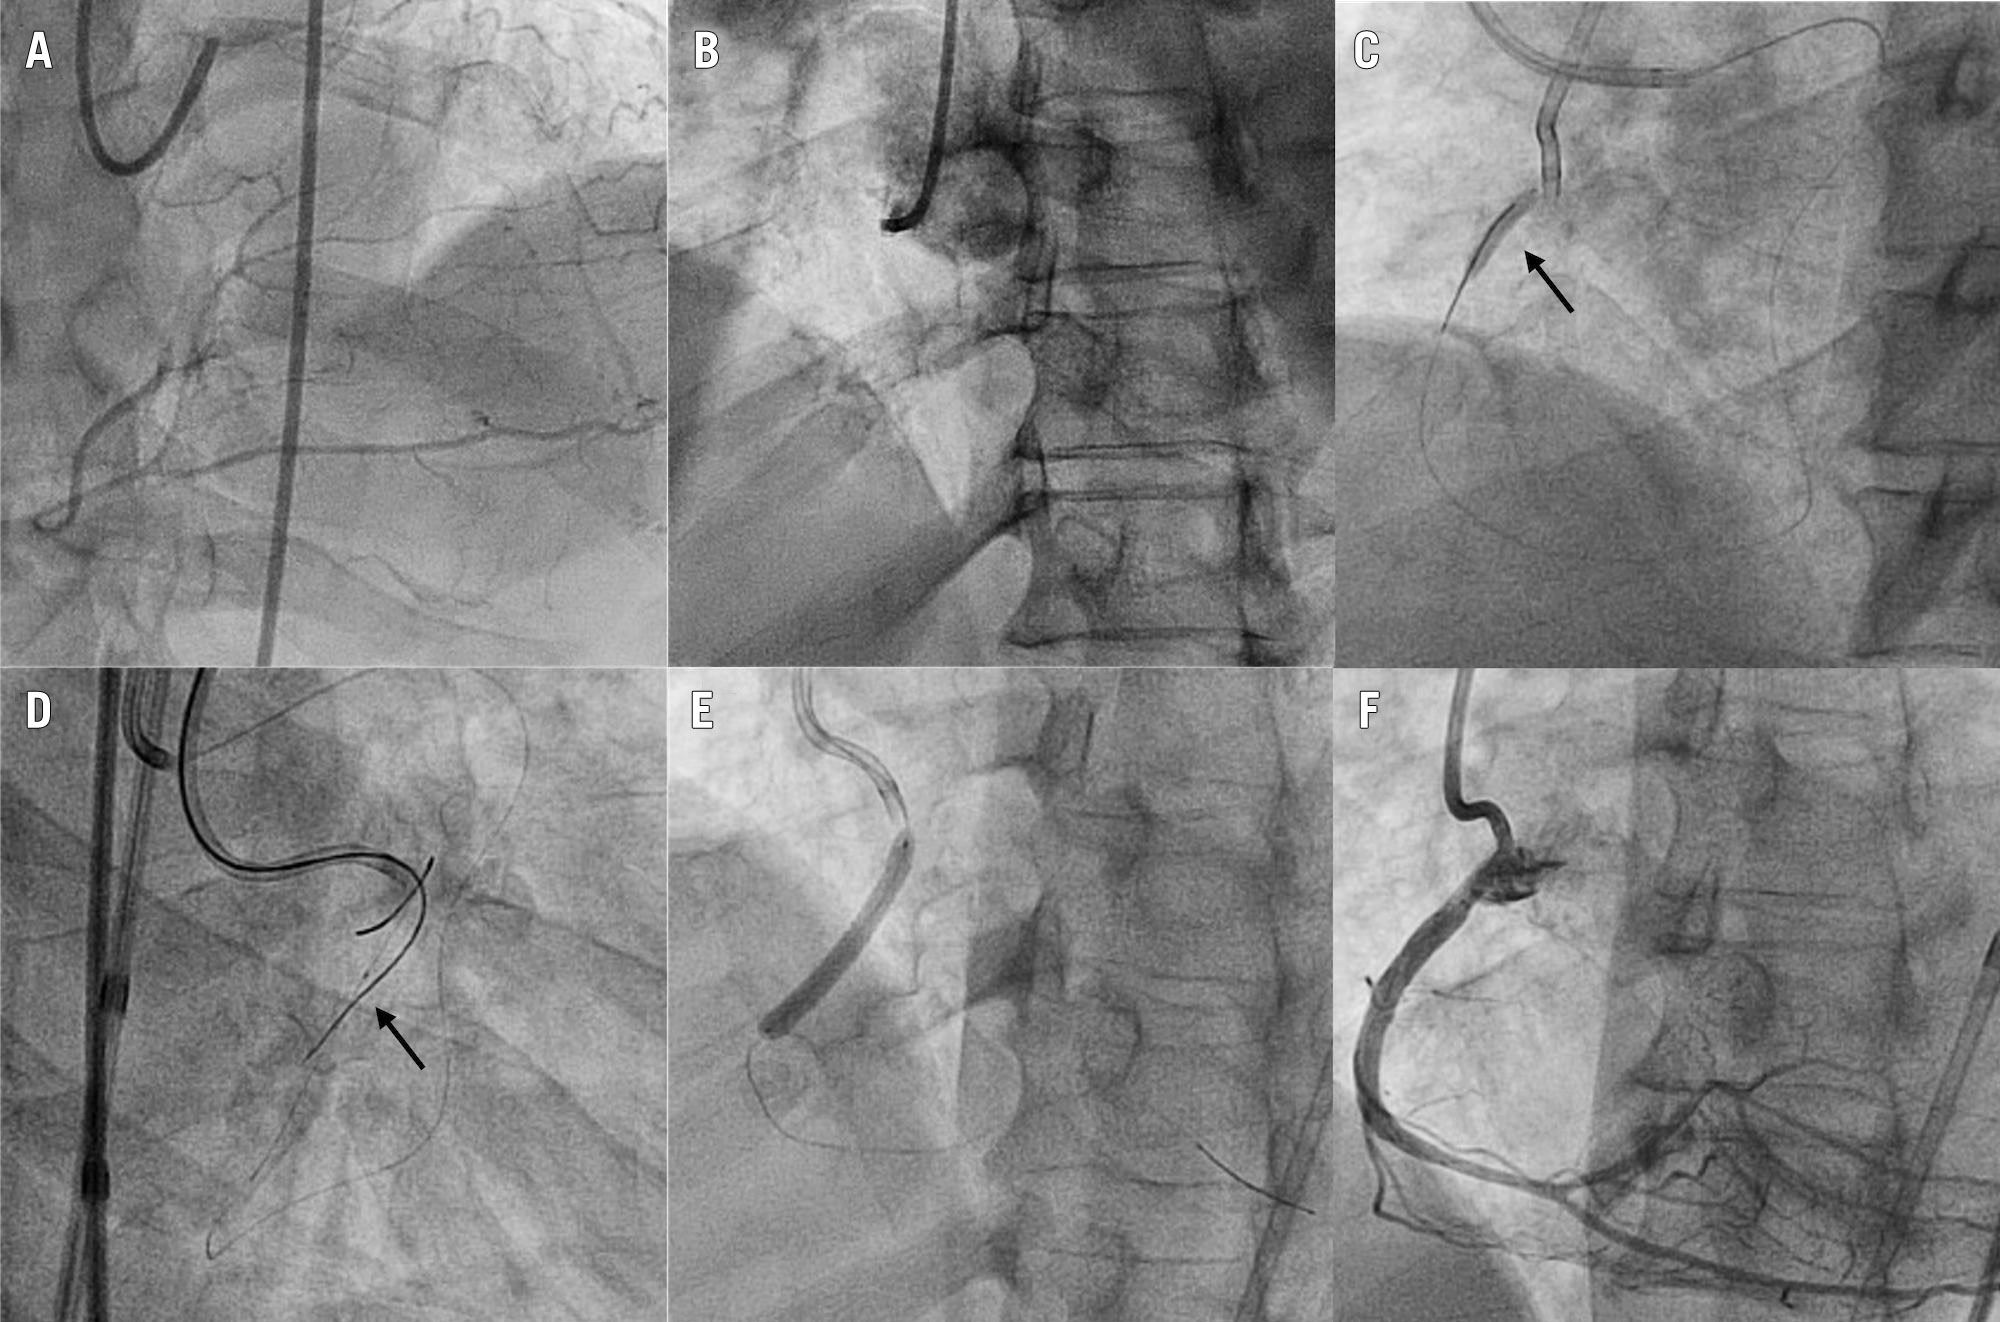

CART was successful in 33 (73.3%) cases. Even when it was not successful (12 cases), CART facilitated advancing retroÂgrade gear to successfully perform reverse CART in 5 cases (41.7%). Figure 4 presents a typical case example of CART.

Figure 4. Case example: CART for flush ostial CTO of the right coronary artery. A) Extensive septal collateralisation from the left anterior descending artery. B) Flush ostial RCA CTO. C) Using an antegrade AL 0.75 and a retrograde EBU 3.5 guide set-up, a 3.0x20 mm balloon (arrow) is advanced from retrograde via the septal collaterals and inflated in the proximal RCA. D) After balloon deflation, a Gladius Mongo (Asahi Intecc) (arrow) can be advanced antegradely into the distal true lumen. E) Stenting. F) Final angiographic result. AL: Amplatz left; CART: controlled antegrade and retrograde subintimal tracking; CTO: chronic total occlusion; EBU: Extra Backup; RCA: right coronary artery